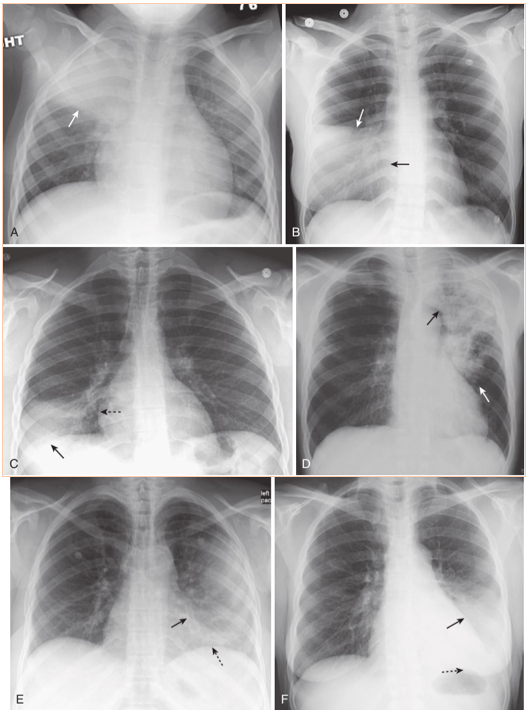

Composite appearances of lobar pneumonias.

A,Right upper lobe. The disease obscures (silhouettes)the ascending aorta. Where it abuts the minor fissure, it produces a sharp margin (white arrow). B,Right middle lobe. The disease silhouettes the right heart border (solid black arrow). Where it abuts the minor fissure, it produces a sharp margin (solid white arrow). C,Right lower lobe. The disease silhouettes the right hemidiaphragm (solid black arrow). It spares the right heart border (dotted black arrow). D,Left upper lobe. The disease is poorly marginated (solid white arrow)and obscures the aortic knob (solid black arrow). E,Lingula. The disease silhouettes the left heart border (solid black arrow)but spares the left hemidiaphragm (dotted black arrow). F,Left lower lobe. The disease obscures the left hemidiaphragm (dotted black arrow)but spares the left heart border (solid black arrow).